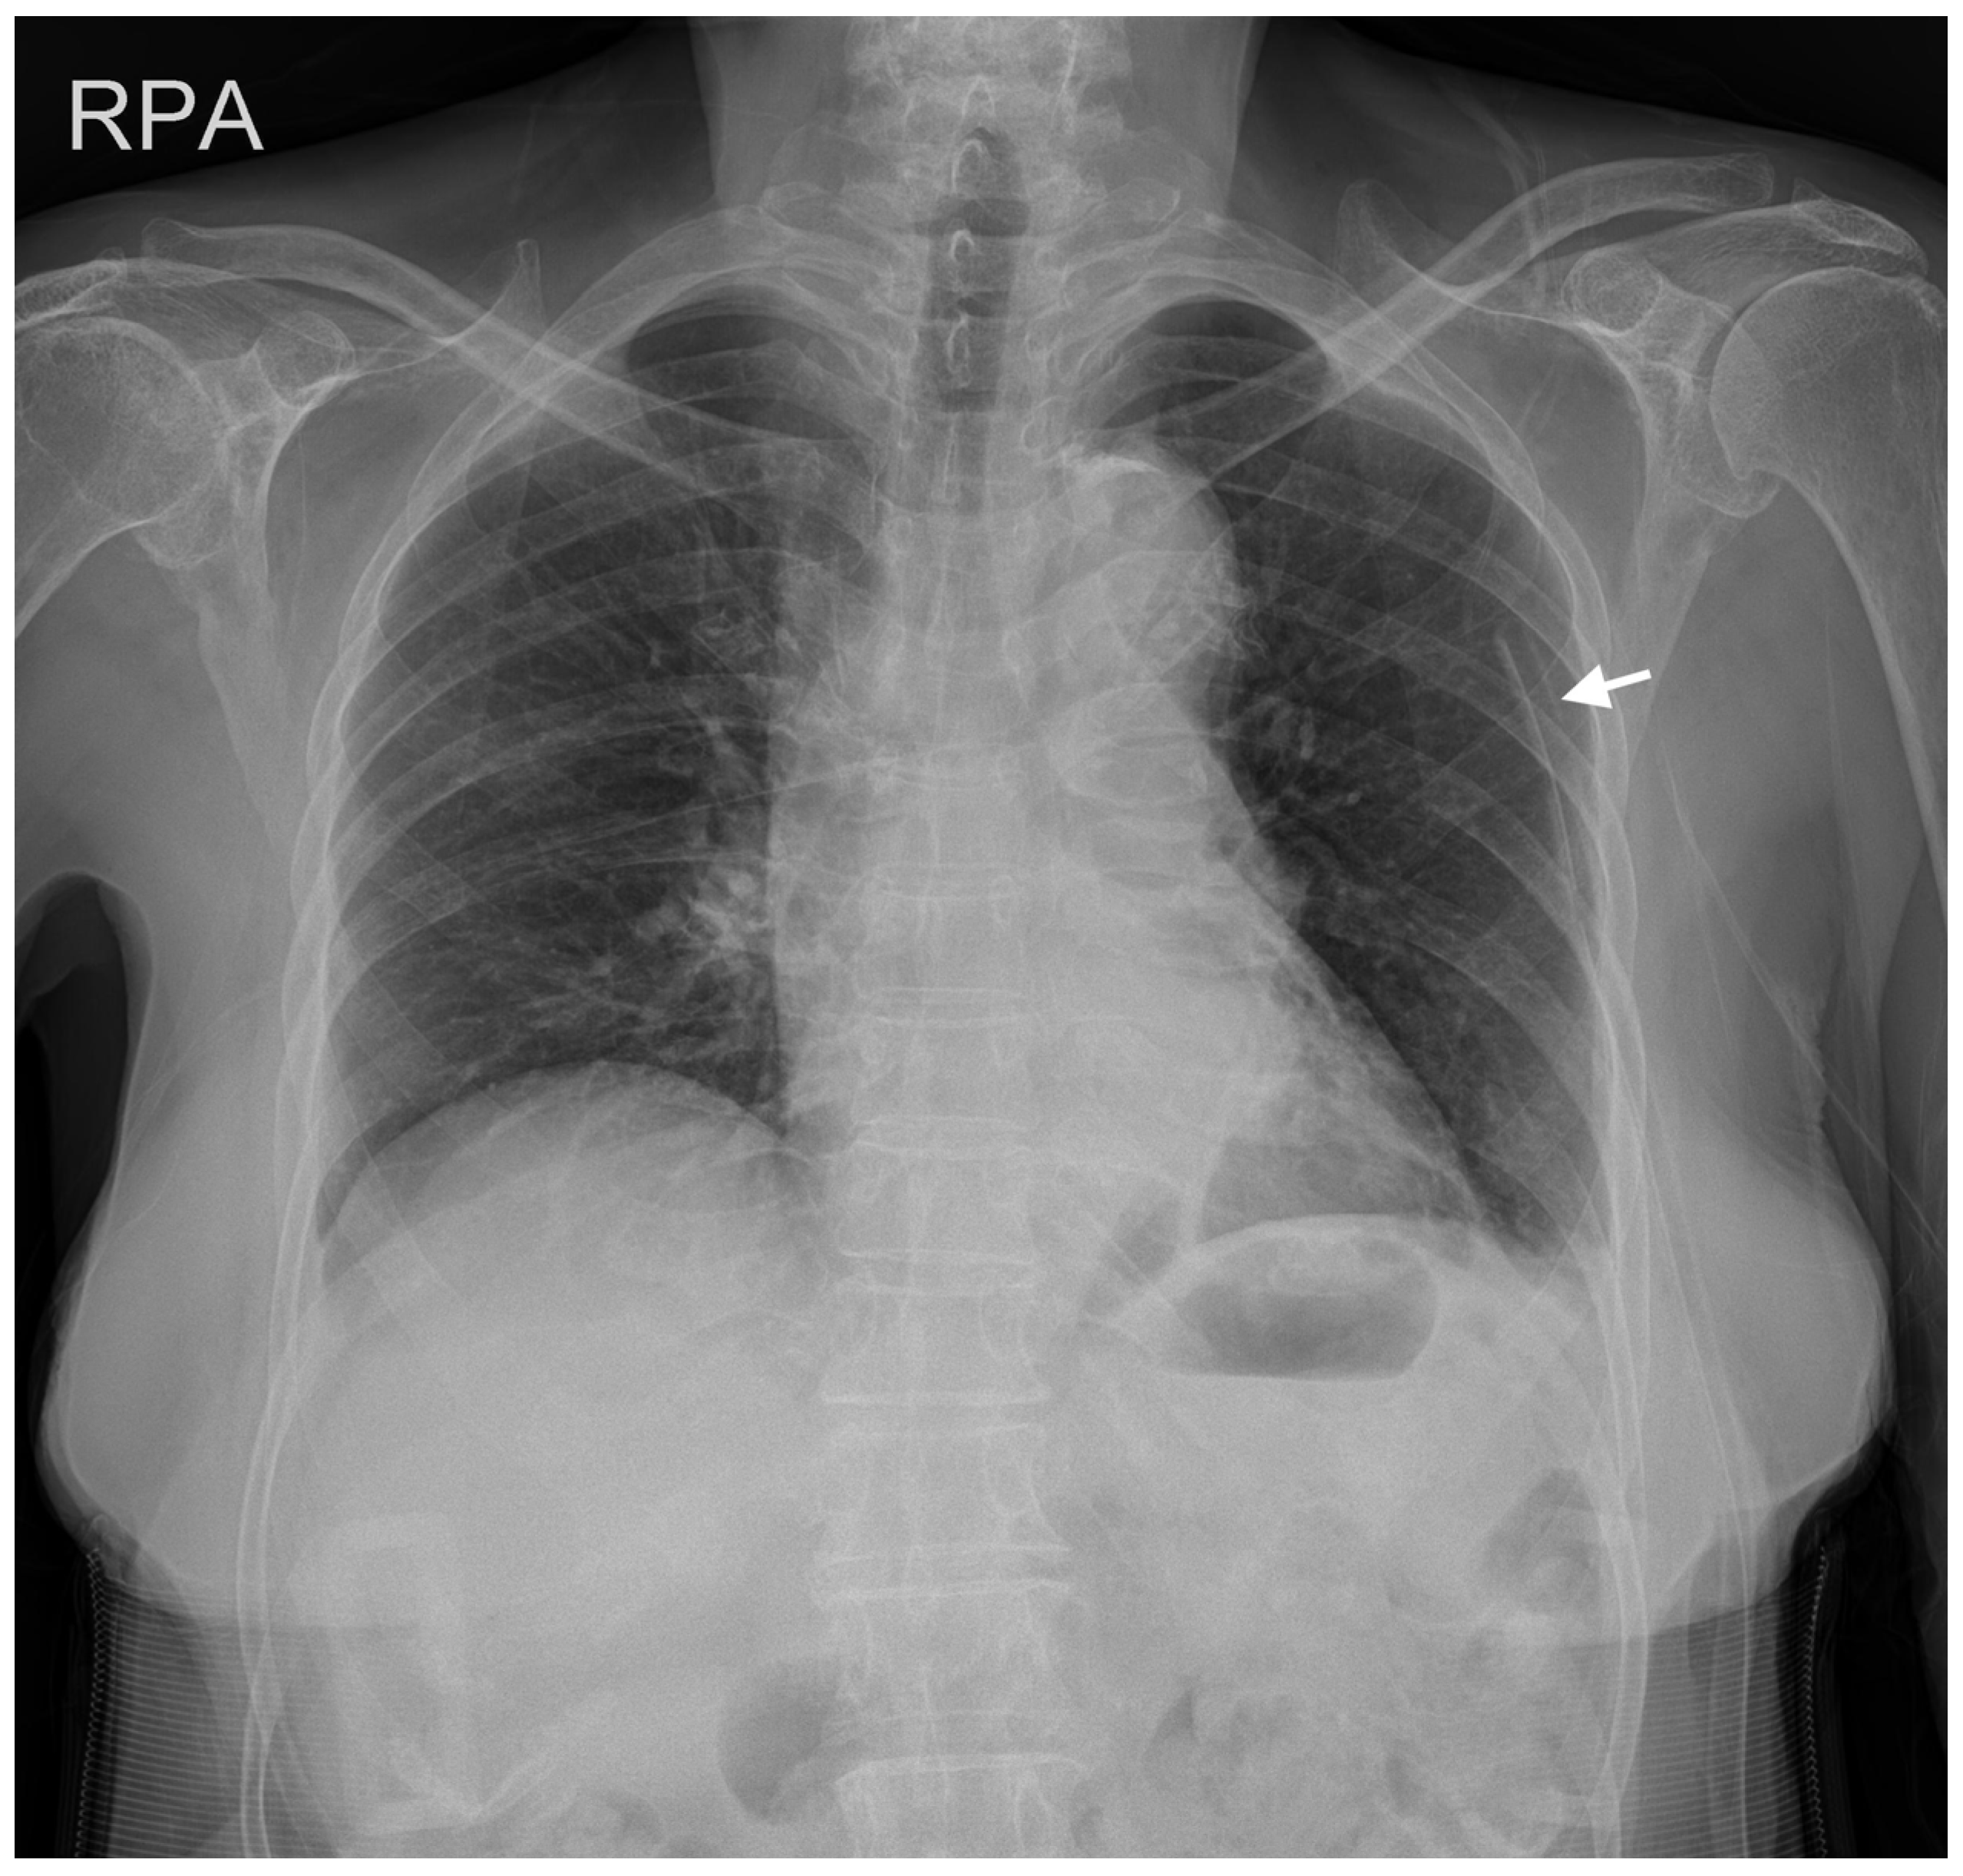

2. Case Description